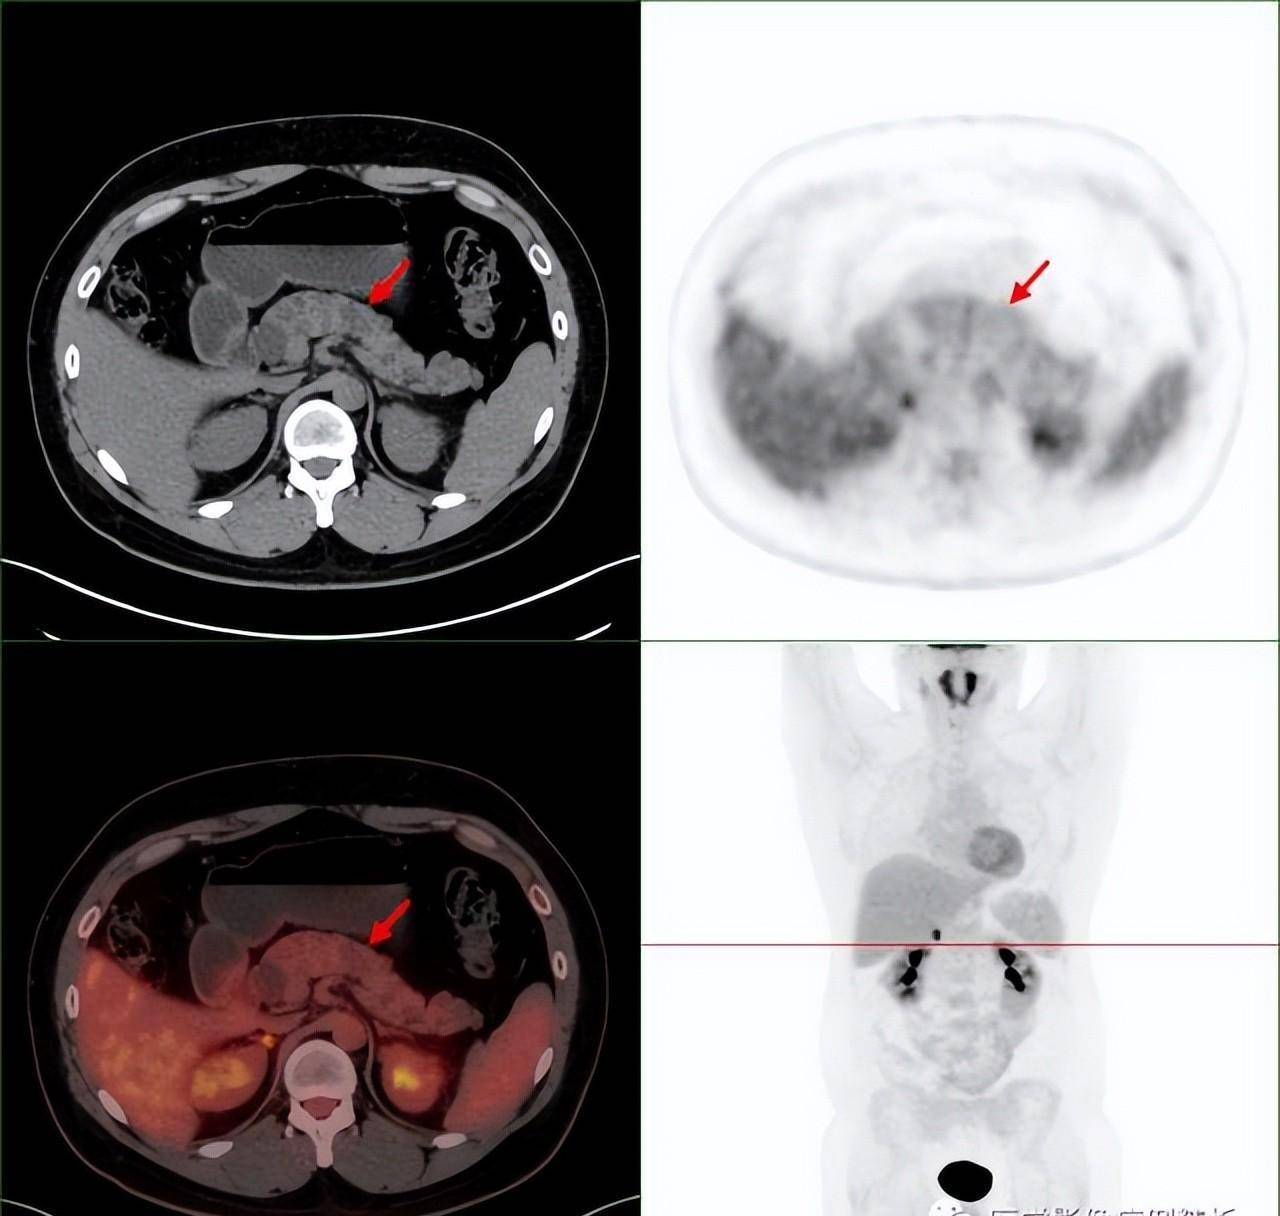

单纯肾病吗?vhl综合征(林岛综合征)pet-ct影像诊断及鉴别诊断